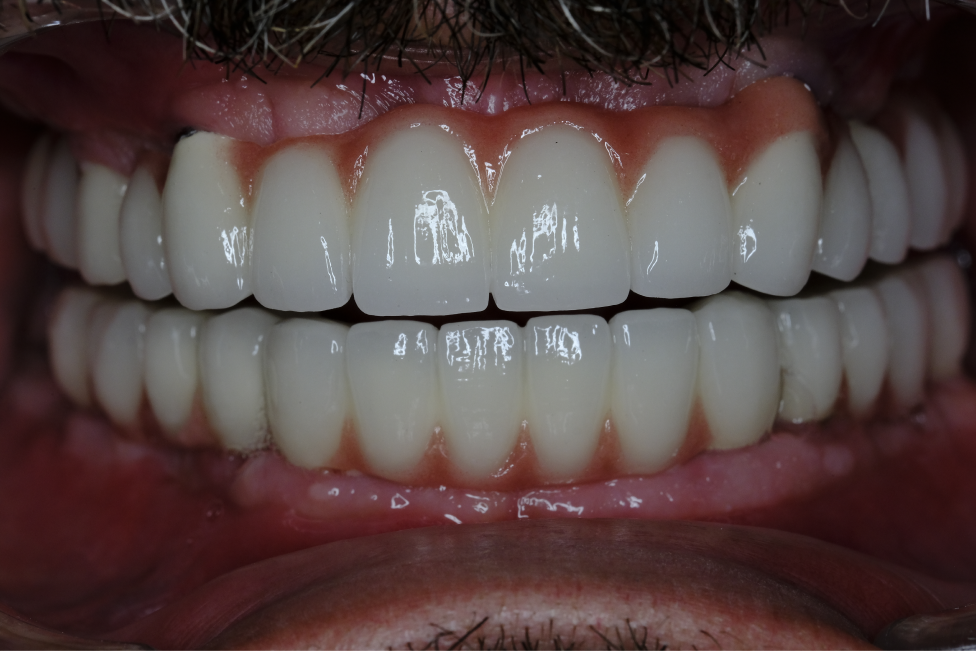

Three months later, after the completion of implant osseointegration, the patient's need for prostheses was evaluated. Zirconium prostheses were preferred to meet the patient's aesthetic and functional requirements. Zirconium prostheses offer advantages in terms of durability and natural appearance.

The application of Naxis implants and zirconium prostheses, taking into account the patient's specific conditions, resulted in a successful treatment outcome. This approach may provide a reliable option for implant treatment in patients with periodontal problems or systemic health issues.